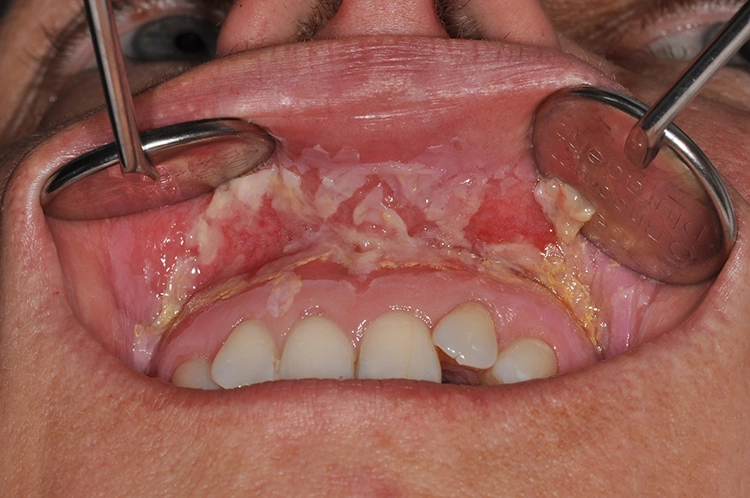

Pathophysiologisch kommt es nach der Initiationsphase im Rahmen der Therapieapplikation (Bestrahlung/Chemotherapie) auf subzellulärer Ebene zur Aktivierung verschiedener Signalwege, die dann eine Entzündungsreaktion mit Ulzeration des mukosalen Epithels und konsekutiver Superinfektion durch Bakterien der Mundflora hervorruft, bis letztlich die Ausheilung stattfindet [3] (Abb. 1).

Die orale Mukositis stellt eine schmerzhafte und für Patienten sehr belastende Nebenwirkung dar, da die orale Nahrungsaufnahme und die Mundhygiene schmerzbedingt gestört sein können. Weitere Symptome können ein brennendes Gefühl, Geschmacksverlust, das Gefühl der Mundtrockenheit sowie eine reduzierte Mundöffnung und Zungenbeweglichkeit sein. Bevorzugt tritt die Mukositis im Bereich der Wangenschleimhäute und der Zunge auf.

Nach der Weltgesundheitsorganisation (WHO) und der Radiation Therapy Oncololgy Group (RTOG) lässt sich die orale Mukositis in die Schweregrade 0 bis 4 einteilen:

Grad 0: normal

Grad 1: Wunden, Erytheme

Grad 2: Erytheme, Ulzerationen (feste Nahrung möglich)

Grad 3: Ulzerationen (nur flüssige Nahrung möglich)

Grad 4: Blutende Ulzerationen (keine orale Nahrungsaufnahme möglich)